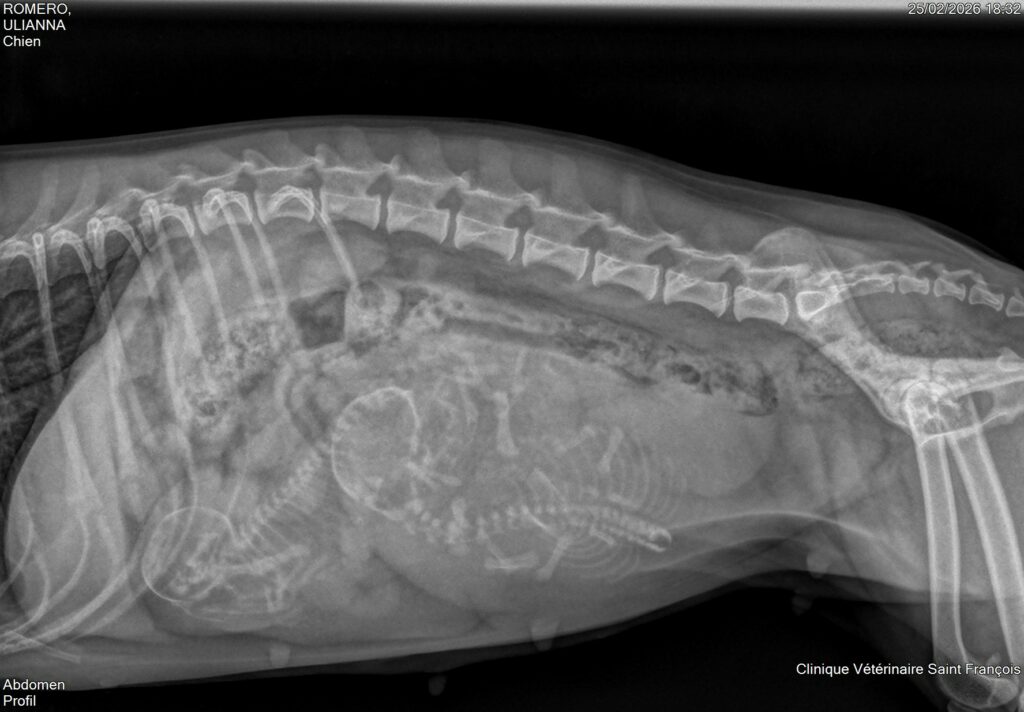

Nous sommes heureux de vous annoncer que Ulianna, notre femelle bichon bolonais, a été saillie avec Quentin Di Chiesanova les 1, 2 et 3 janvier. Une radiographie réalisée le 25 février a confirmé une portée de 2 chiots 🐶🤍.